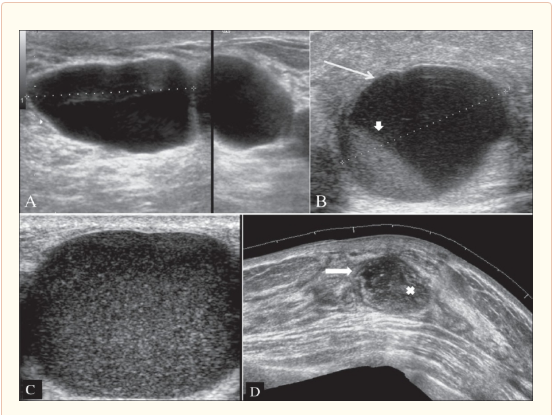

Siêu âm tuyến vú:

Đánh giá những bất thường và chẩn đoán u xơ, nang, xơ hoá,…

Hình 6. Siêu âm tuyến vú